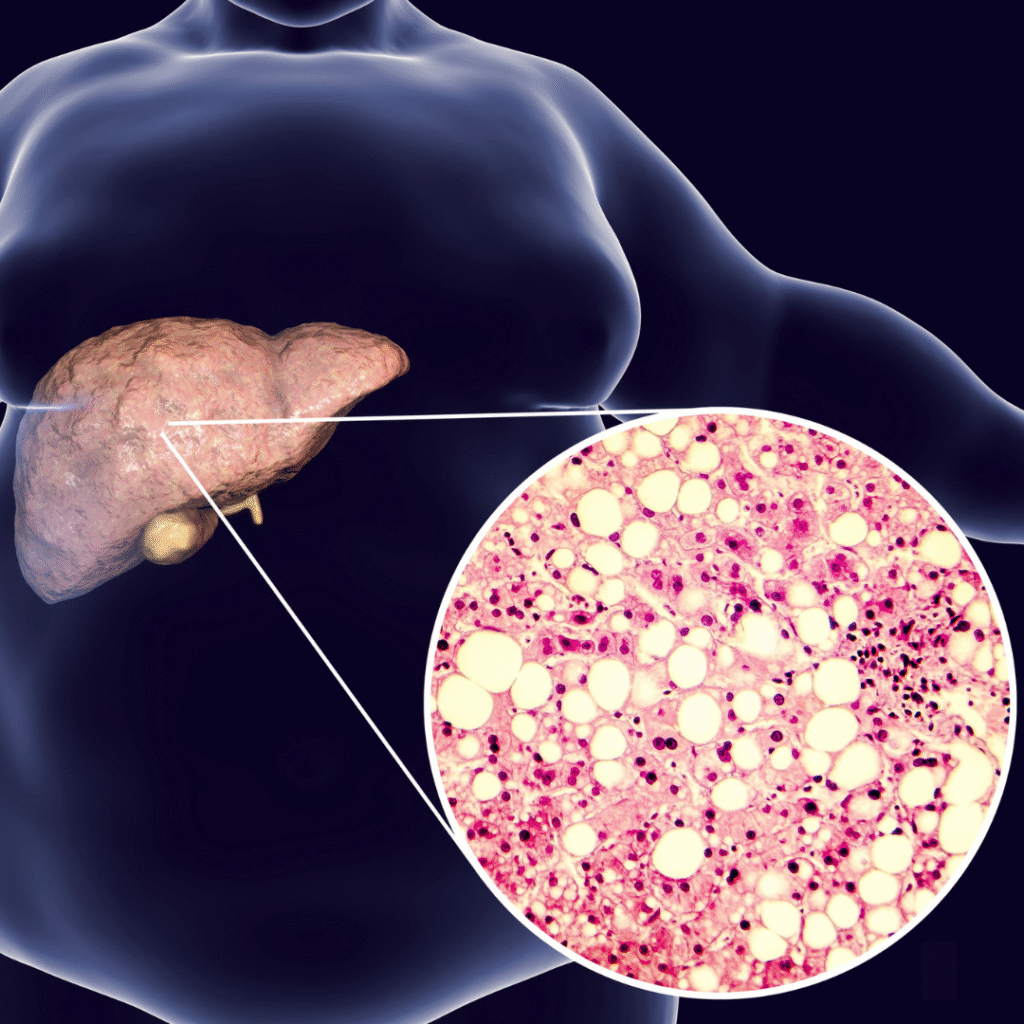

ΗΠΑΤΩΣΗ

Λιπαρό ηπατικό νόσημα

ΟΞΕΙΑ ΦΛΕΓΜΟΝΗ

ΙΝΩΣΗ

Αντικατάσταση ηπατικού παρεγχύματος με ουλώδη ιστό

ΚΙΡΡΩΣΗ

Αποσύνθεση του ήπατος

ΕΞΩΤΕΡΙΚΟΙ ΠΑΡΑΓΟΝΤΕΣ ΠΡΟΚΑΛΟΥΝ ΦΛΕΓΜΟΝΗ ΤΗΣ ΗΠΑΤΙΤΙΔΑΣ ΚΑΙ ΜΕ ΤΟ ΧΡΟΝΟ ΡΑΡΤΙΔΕΙ.